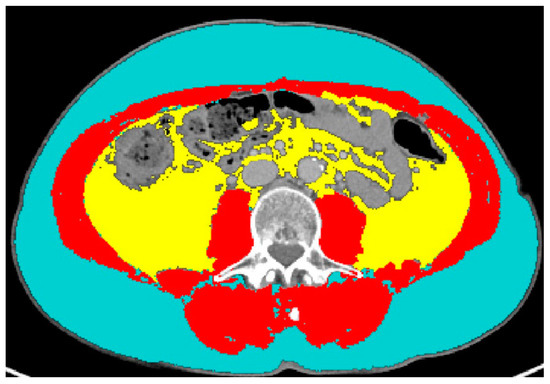

CT examinations were performed on different CT scanners at different institutions, but they were all available in digital format on our PACS. Feature extraction was performed from the portal venous phase of contrast-enhanced series. An axial image at the level of the third lumbar vertebra (L3) was selected and segmented through the Slice-O-Matic software version 5.0 (Tomovision, Montreal, QC, Canada). The software offers the opportunity to perform either semi-automatic or automatic segmentations, both based on different CT attenuation thresholds for skeletal muscle, SAT and VAT (the automatic segmentation tool is available as adjunctive tool commercially from Voronoi Health Analytics Inc., Coquitlam, BC, Canada; https://voronoihealthanalytics.com (accessed on 3 August 2023)) [38]. Accurate segmentations, checked visually after the software’s use, led to the recording of the following numerical data: skeletal muscle area (including the following muscles: psoas, erector spinae, quadratus lumborum, transversus abdominis, external obliques, internal obliques, and rectus abdominis muscles), measured in centimeters squared; skeletal muscle density (measured by Hounsfield units (HU)); subcutaneous adipose tissue (SAT, expressed in centimeters squared); and visceral adipose tissue (VAT, expressed in centimeters squared). An example of segmentations is shown in Figure 1. The lumbar skeletal muscle index (SMI) was calculated by dividing SMA by square height (m2) and reported as cm2/m2. The sex-specific cut-off to define sarcopenia was SMI < 41 cm2/m2 for women of any BMI; it was < 43 for underweight and normal weight men; it was < 53 for overweight and obese men [39].

Figure 1.

Example of segmentation of subcutaneous adipose tissue (light blue), visceral adipose tissue (yellow) and skeletal muscle area (red).